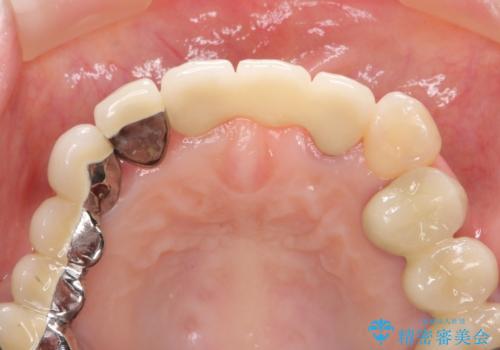

前歯ブリッジのやりかえ

歯肉縁下カリエスも認められるため、挺出を行いセラミックブリッジを審美的に新製します。

- 47万円(仮歯×3・ファイバーコア×2・ジルコニアクラウン×3 歯の挺出)費用は治療当時の料金となります

虫歯が深くなった場合、挺出や歯周外科を行い歯周組織の状態を改善することでより安定した状態で予知性の高いセラミックブリッジを製作することが可能となります。